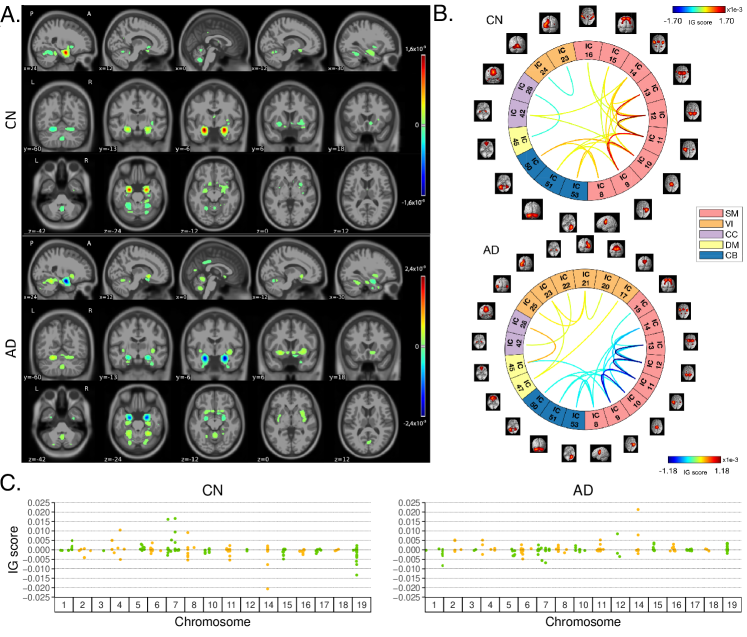

Figure 4: Overview of IG attribution maps for the classification Task 1, AD detection. All the IG maps are presented for the correctly classified CN and AD subjects in the testing set. A. Average sMRI-IG maps, thresholded to retain IG scores exceeding the 99.5thsuperscript99.5𝑡99.5^{th} percentile and overlaid to MNI152152152 template; B. Average fMRI-IG derived connectograms, thresholded to retain the connections with an associated IG score over the 98thsuperscript98𝑡98^{th} percentile; C. Average SNPs-IG scores highlighting the SNPs with an associated positive IG score exceeding the 65thsuperscript65𝑡65^{th} percentile, SNPs are grouped by chromosome.

Fig. 4 shows the average IG maps obtained for the AD detection task and for each input channel, averaged over the correctly classified subjects per class (test set). The jet colorbar was used to highlight the attribution scores, where red and blue correspond to positive and negative attribution values, respectively. In detail, Fig. 4A shows the average sMRI-IG maps for the correctly classified CN and AD patients, overlaid onto the MNI152152152 template (1.5 mm). A thresholding was applied in order to visualize only the relevance scores above the 99.5thsuperscript99.5𝑡99.5^{th} percentile of the relevance distribution, followed by a Gaussian smoothing with FWHM = 3 mm for visualization purposes. It is evident that the subcortical regions, in particular the hippocampus, are associated with high IG scores in absolute value, with the highest positive (negative) values for CN (AD). Cortical regions generally showed almost null relevance for both the CN and the AD-derived sMRI-IG maps. Of note, higher absolute values were found for the AD maps compared with the CN ones.

Moving to the fMRI-IG qualitative analysis, Fig. 4B shows the average connectograms for CN and AD subjects, including only the connections above the 98thsuperscript98𝑡98^{th} percentile of the relevance distribution. The ICs-brain region correspondences are detailed in Supplementary Table 222.

The most relevant RSNs were the primary information processing-related networks (SM and VI) followed by multisensory integration networks (CC and DM), and cerebellum (CB), showing high relevance for both the CN and the AD-derived fMRI-IG. In particular, the 535353% of the most relevant connections for the CN group belong to the SM network, as opposed to the 383838% found for the AD-derived fMRI-IG maps. On the other hand, the VI was highly involved for AD subjects, with the 282828% of relevant connections belonging to this RSN, differently from the CN where only 222 VI ICs resulted as relevant. Of note, a total of 151515 ICs were marked as relevant for both the CN and the AD-derived fMRI-IG, but with an opposite sign.

More in detail of the relevant connections between the different ICs, the CN subjects showed positive relevant intra-network connections in the CB and SM RSNs, with particularly high scores for the connections involving the post/paracentral and parietal gyri (ICs 9,10,11,12,139101112139,10,11,12,13). Inter-network positively relevant connections were also found between the SM and the CB, and the SM and the CC RSNs. Only two negative IG scores were instead retrieved, related to an intra-network connection in the VI network and to an inter-network connection between CC and DM.

A similar pattern was found for the AD fMRI-IG relevant connections but with generally opposite IG-associated scores. In detail, negative relevance was mainly found for both the intra- and inter-network connections encompassing the SM and CB RSNs, with an intra-connection in SM (ICs 1112111211-12) showing the highest negative relevance between the same ICs highlighted with the opposite sign in the CN. On the contrary, positive relevance was recorded for the connections between multiple VI ICs, in particular involving right middle occipital gyrus (IC 212121) with cuneus (IC 202020), inferior occipital gyrus (IC 232323), and middle temporal gyrus (IC 252525) as well as the inter-network connections VI-DM and CC-DM, with the latter being the most relevant one.

Finally, concerning the SNPs-IG qualitative analysis, Fig. 4C presents a Manhattan plot including only the SNPs with an attributed positive IG score higher than the 65thsuperscript65𝑡65^{th} percentile, grouped by chromosome. The y-axis reports the associated IG score. A complementary trend between the IG values associated with the SNPs was found between the two classes. This was particularly evident for Chr 111, 777, 111111, 141414, 151515 and 191919. A generally high involvement of the Chr 777, 888, 111111, 141414, and 191919 was present for both the AD and CN, with the majority of SNPs selected in these Chr showing high IG scores, either positively or negatively. Of interest, the most relevant SNPs, with positive IG were found in Chr 444, 777, and 888 for the CN and in Chr 121212 and 141414 for the AD. On the contrary, the most negatively relevant SNPs for CN were found in Chr 141414 and 191919, as opposed to AD where they were mainly in Chr 111, 666, and 777.